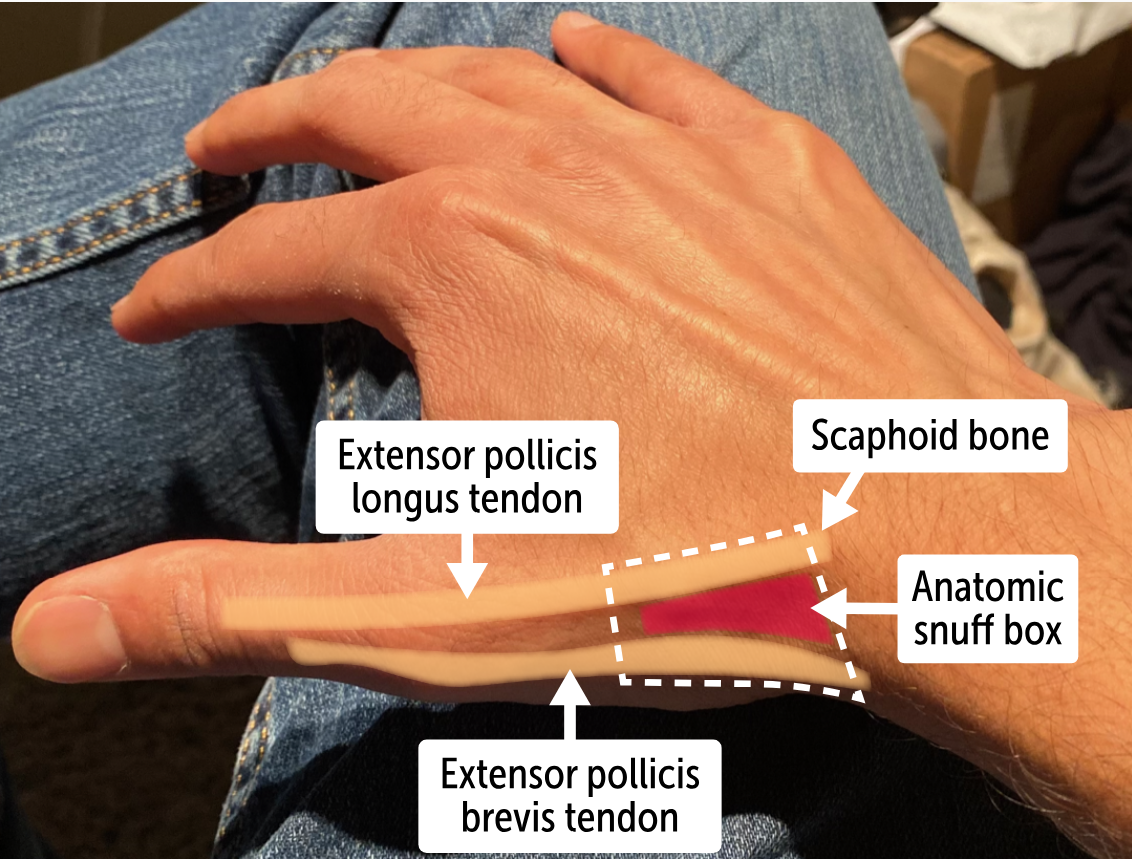

The bone forms the floor of the ____________, an anatomic landmark formed by the tendons of the extensor pollicis longus, the extensor pollicis brevis, and the abductor pollicis longus muscles

anatomic snuff box

What bone lies in the anatomic snuff box?

The carpal scaphoid bone is found in the anatomic snuff box.